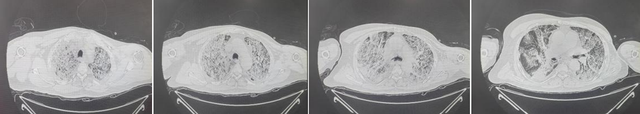

患者入院当天CT

68岁的王先生到我院整形外科为烫伤皮肤换药时,接诊医师发现其存在明显呼吸困难,经皮血氧饱和仅50%,紧急转入急诊。急诊胸部CT显示,双肺弥漫性渗出,多项指标提示“重症肺炎、急性呼吸窘迫综合征、多脏器功能衰竭”。急诊立即实施气管插管、有创呼吸机辅助通气及抗感染治疗,但即使在高参数呼吸机支持下,患者血氧饱和度仍仅维持在66%左右,随后转入重症医学科进一步抢救。

患者双肺呈“白肺”改变,病情危重复杂。为快速明确致病菌,医疗团队紧急对肺泡灌洗液和血液进行二代宏基因测序,结果确诊为“猫立克次体、纹带棒状杆菌”。在药学部副主任、临床药师顾红燕的指导下,团队迅速制定精准抗感染方案,实施针对性治疗。